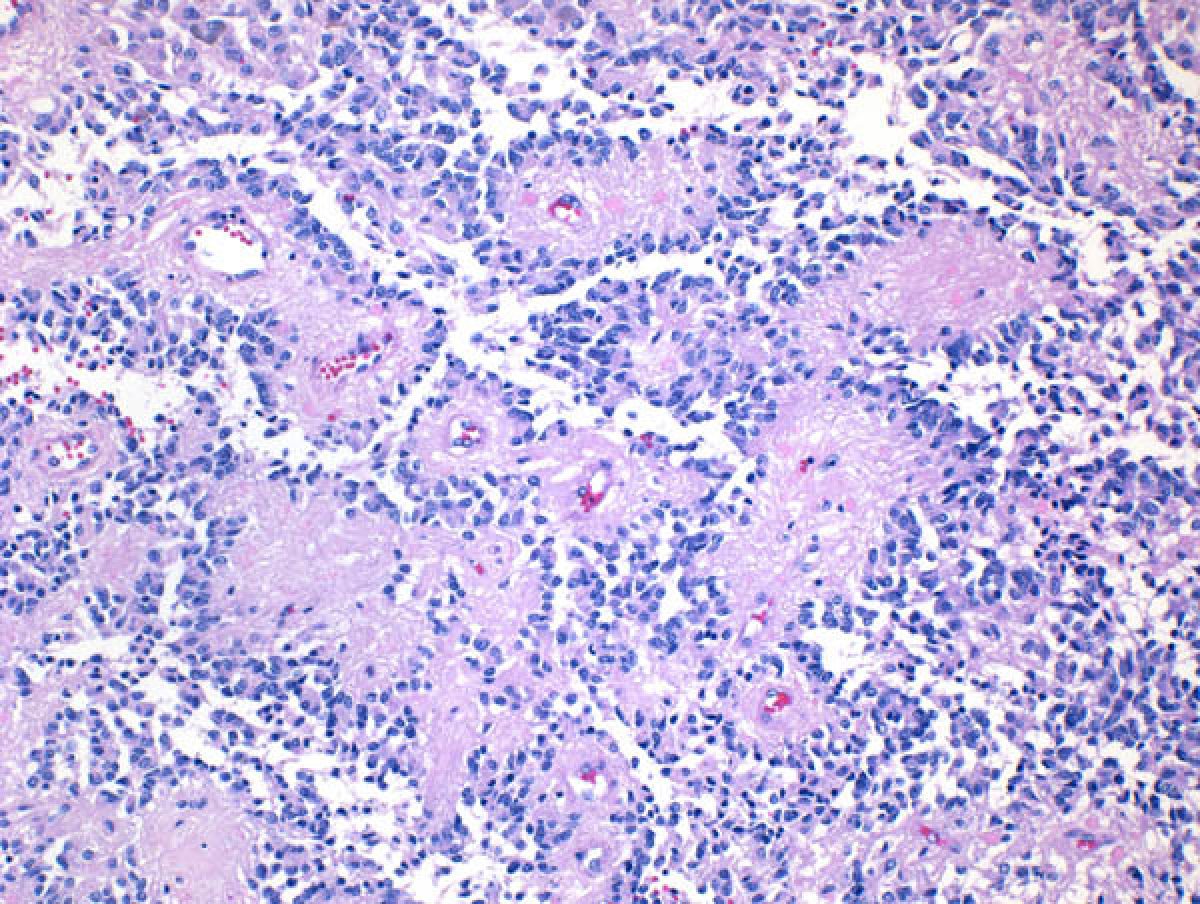

Gliomas represent the largest group of primary brain tumors and resemble glia, supportive cells encountered in the brain parenchyma. Astrocytomas and oligodendrogliomas are two glioma subtypes. These tumors may be low grade or high grade based on their potential aggressiveness, and include the highly malignant glioblastoma which has a high proliferative rate under the microscope, as well as other features of aggressiveness including microvascular proliferation and necrosis.